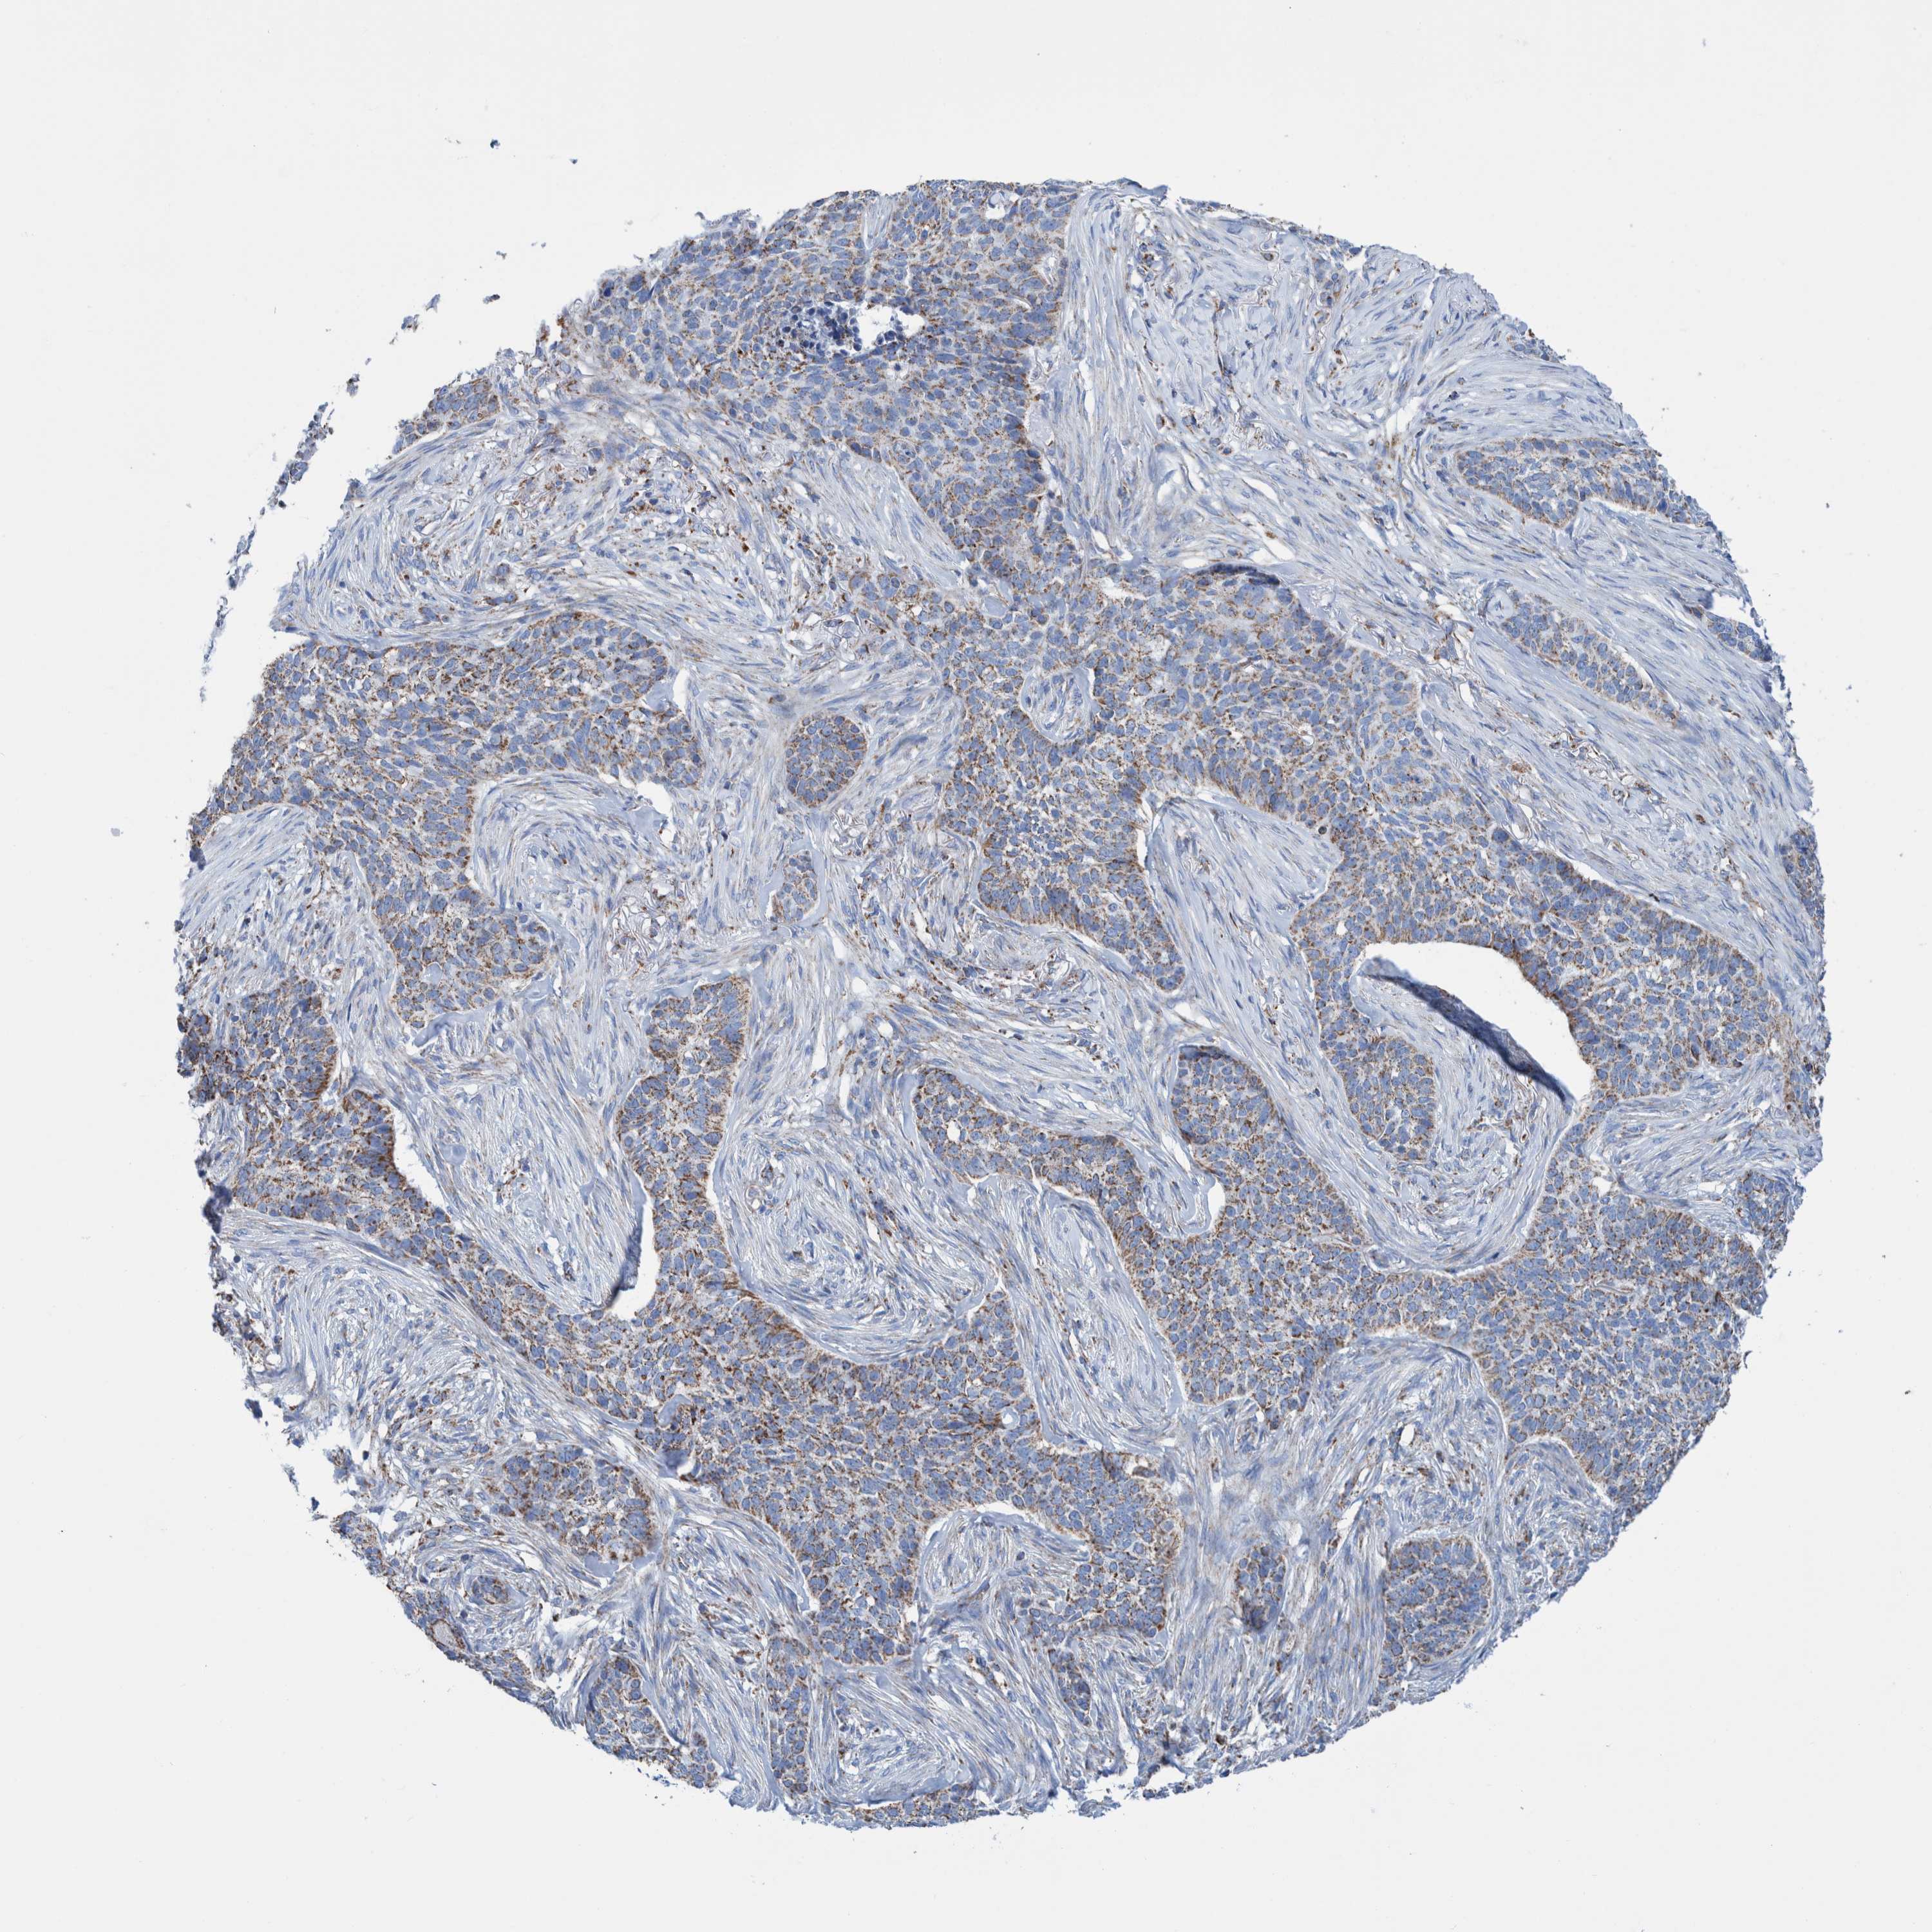

SKIN CANCER - Protein expressioni

A mouse-over function shows sample information and annotation data. Click on an image to view it in a full screen mode. Samples can be filtered based on level of antibody staining by selecting one or several of the following categories: high, medium, low and not detected. The assay and annotation is described here.

Each image is clickable and will lead to virtual microscopy that enables deeper exploration of all samples and also displays staining intensity scores, fraction scores and subcellular localization as well as patient and tissue information for each sample.

Antibody HPA023160

Basal cell carcinoma